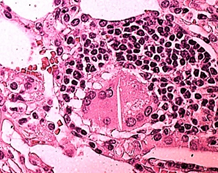

Il paziente della Figura 1 fuma 20/sigarette/tabacco/die da 20 anni;sniffa cocainauna volta al giorno da 10 anni. Tossicologico urine positivo alla cocaina. La TC-Torace mostra ILD,il BAL alveolite linfocitaria CD4, aumento neutrofili ed eosinofili, numerose cellule giganti, mastociti e corpi birifrangenti. Lâistologico della resezione atipica della Lingula mostra: fibrosi interstiziale, focolai granulomatosi. La valutazione del vetrino al microscopio a luce polarizzata mostra birifrangenza di inclusioni aghiformi (Figura 1). Non potendo derivare da altre fonti, bisogna attribuirle alla cocaina tagliata con talco o cellulosa. Essendo cristalli sottili ed allungati, di dimensioni fra 10 e 40 micron e morfologia di fibre organiche, esse sono di cellulosa. La diagnosi alla dimissione è stata: fibrosi e granulamatosi polmonare da cocaina tagliata con cellulosa.

DIP compare in 5/10 (50%) con tessuto operatorio cannabinoidipositivo, 1/5 (20%) con tessuto operatorio cannabinoidinegativo. Accumulo di Macrofagi nei cinque pazienti con DIP cannabinoidipositivi; assenzanellâunico con DIP cannabinoidinegativo.Supportando la cannabis nel provocare DIP, avvalorata dalla giovane etĂ 24-27 anni. Nella DIP da altre cause, l'etĂ media di inizio dei sintomi è tra 40 e 60 anni. Sono responsabili anche additivi, adulteranti e sostanze da taglio: cellulosa, talco, amido (Figura 1). La loro ricerca nel granuloma appare cruciale per una diagnosi eziologica corretta.